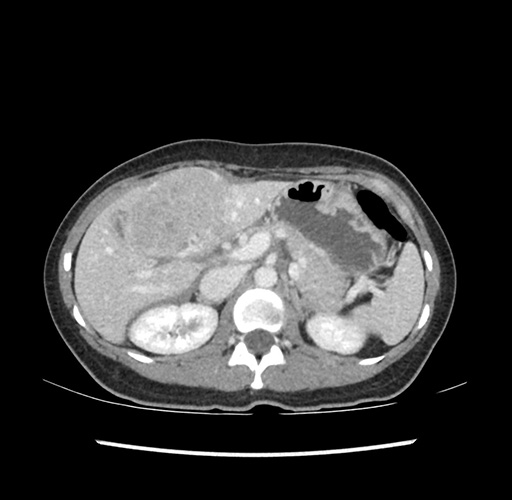

Imaging Analysis

Look through the patient's CT scan to identify any areas of concern for the necessary procedure.

Based on your CT findings, which issue(s) would give reason for "planned slowing down moment(s)" in this case?